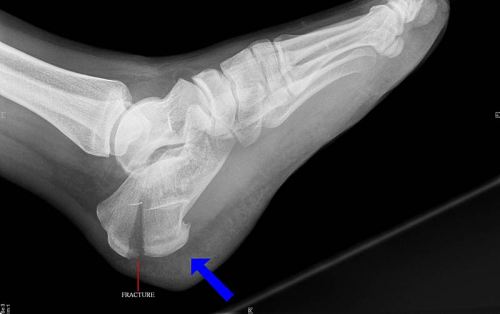

Перелом пяточной кости со смещением и без него Автор Екатерина Михайлюк | дата обновления 19.01.2017Мой мирВконтактеОдноклассники Рубрика: Поделись в соцсетяхВконтактеОдноклассники